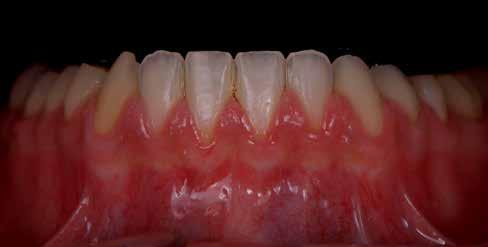

nak megfelelően – előkészítjük (orthofoszforsavval történő savazás, lemosás, szárítás és bond réteggel történő fedés). Ezzel egyidejűleg a ragasztásra kerülő héjak is előkészítésre kerülnek (hidrofolysavval történő savazás, lemosás, szárítás, szilanizálás, bond réteggel történő fedés, és végül az alkalmazni kívánt ragasztóanyag felvitele). Ezután a héjakat a fogak felszínén egyesével pozicionáljuk, majd néhány másodpercen keresztül polimerizációs lámpa segítségével megvilágítjuk. Ezt követően a kifolyó ragasztófelesleget eltávolítjuk, majd elvégezzük a restaurátumok végső polimerizálását. A héjak végleges rögzítését követően az esetlegesen visszamaradt ragasztómaradványok eltávolításra kerülnek, valamint ellenőrizzük az okklúzió és artikuláció közben létrejövő fogérintkezéseket. Az optimális esztétikai eredmény biztosítása érdekében kiemelt jelentősége van a papillák helyreállításának (rózsaszín esztétika). A modern fogorvoslás egyik kiemelt célja a fehér- és rózsaszín esztétika közti harmonikus egyensúly megteremtése. A papillák színe, nagysága és szimmetrikus megjelenése meghatározó szerepet tölt be a rózsaszín esztétika kialakításában. Az íny lefutása ugyancsak rendkívül jelentős mértékben befolyásolja a páciens fogazatának esztétikus megjelenését.